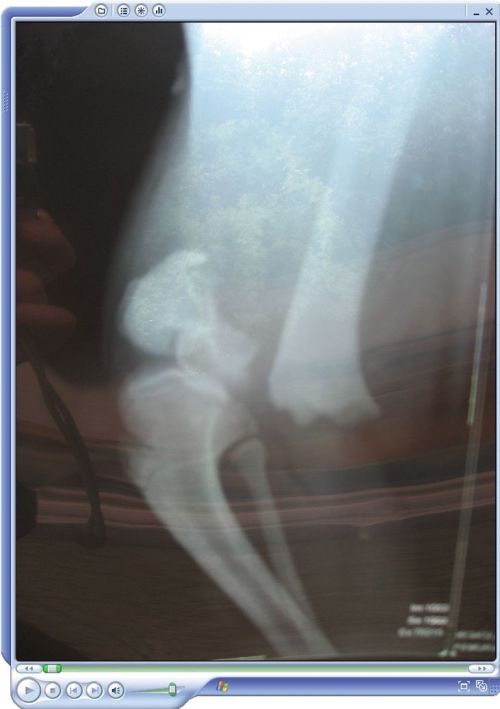

X光图...冲动是魔鬼啊